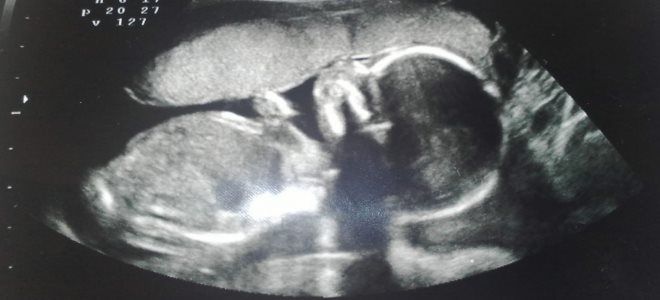

УЗИ на 29 неделе беременности

УЗИ на 29 неделе беременности – это исследование, которое выполняется по конкретным медицинским показаниям. Чаще всего его рекомендуют женщинам с тазовым предлежанием, чтобы выяснить, произошло ли изменение положения плода на головное.

К другим причинам для проведения обследования можно отнести:

- выявленные аномалии на первом и втором скринингах;

- высокий риск возникновения угрозы прерывания беременности;

- частичное отделение плаценты.